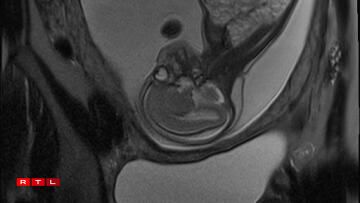

Lis was therefore referred to the Centre Hospitalier de Luxembourg (CHL), where further examinations led to a diagnosis. Noa was found to have a congenital pulmonary airway malformation (CPAM). Doctors explained that a large mass of cysts had formed in his chest, compressing his heart and disrupting his circulation. This, in turn, caused the fluid retention observed during the initial scan.

In Noa’s case, the CPAM was caused by a malformed aorta: a blood vessel had branched toward the lungs and was feeding the cysts. The condition is known as a sequestration. Professor Kohl proposed the following intervention:

“He would go through my abdomen with two small incisions to reach the amniotic sac, then pass through Noa’s chest to the heart, where he would cauterise the blood vessel that was feeding the cysts using a small electric current. From there, we could hope that the cysts would shrink and the lung could begin to develop”.